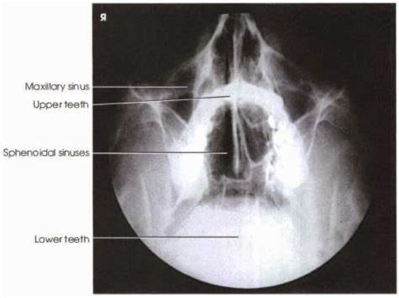

Submentovertical of Ethmoidal & Sphenoidal Sinuses

Submentovertical of the ethmoidal and sphenoidal sinuses